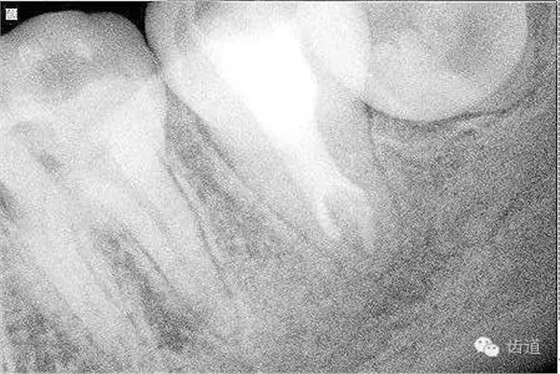

2. 術(shù)后半年X線檢查,可見(jiàn)根尖周膜連續(xù)性恢復(fù),根尖周透射影消失

檢查:術(shù)后半年回訪,37牙體及合面嵌體未見(jiàn)缺損及裂紋,邊緣密合,未探及繼發(fā)齲,探痛-,叩痛-,松動(dòng)-,冷水刺激痛-,未探及牙周袋及附著喪失,牙齦無(wú)紅腫,X線片檢查示根尖周膜連續(xù)性恢復(fù),根尖周透射影消失。